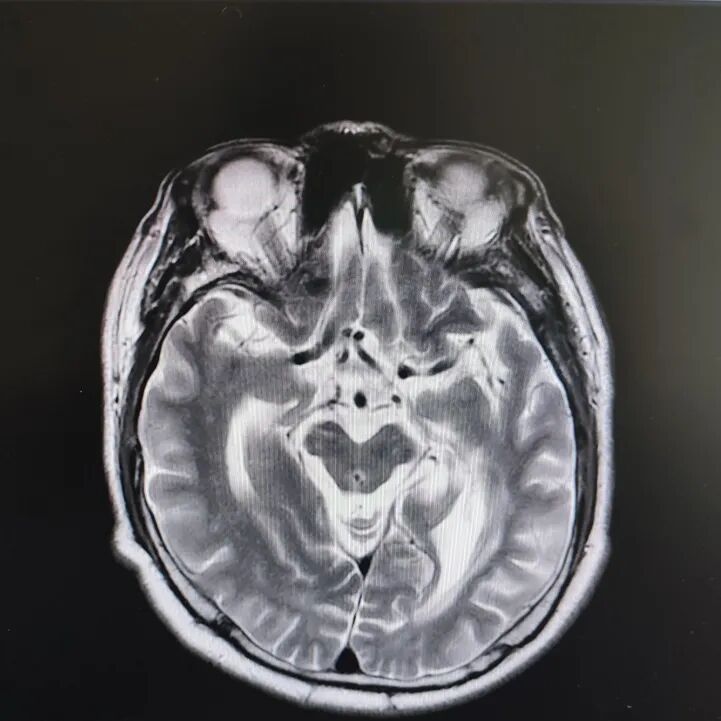

病房里還有另一位患者,來的時候情況更讓人揪心:反應(yīng)遲鈍,表情呆滯,行動緩慢。頭顱核磁顯示腦萎縮明顯,但查體發(fā)現(xiàn)肌張力、計算力、記憶力、定向力均正常,不符合典型血管性癡呆或阿爾茨海默病表現(xiàn)。

患者頭部磁共振影像